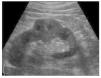

Se realiza entonces nefrectomía derecha, sin complicaciones durante la cirugía o después de la misma, llamando la atención el reporte de patología número 1735-12: "Se recibió pieza patológica identificada como riñón derecho, en donde se observa tumor de 5 x 5 cm de consistencia firme grisáceo amarillento, que ocupa desde la zona medular hasta el polo inferior; al corte y tinción de hematoxilina & eosina de 40 x 0.65: lesión neoplásica que forma túbulos, separados por un estroma fibroblástico abundante, revestidos de células pleomórficas de citoplasma abundante, eosinófilo y núcleos grandes y redondos, rodeados de una reacción desmoplásica prominente; su extensión comprende desde la médula hasta la capsula de Gerota sin rebasarla, hilio renal y ganglios linfáticos, sin infiltración neoplásica" (fig. 4).

Figura 4. Nótese la disposición tubular de la lesión con núcleos prominentes y nucléolos hipercromáticos.